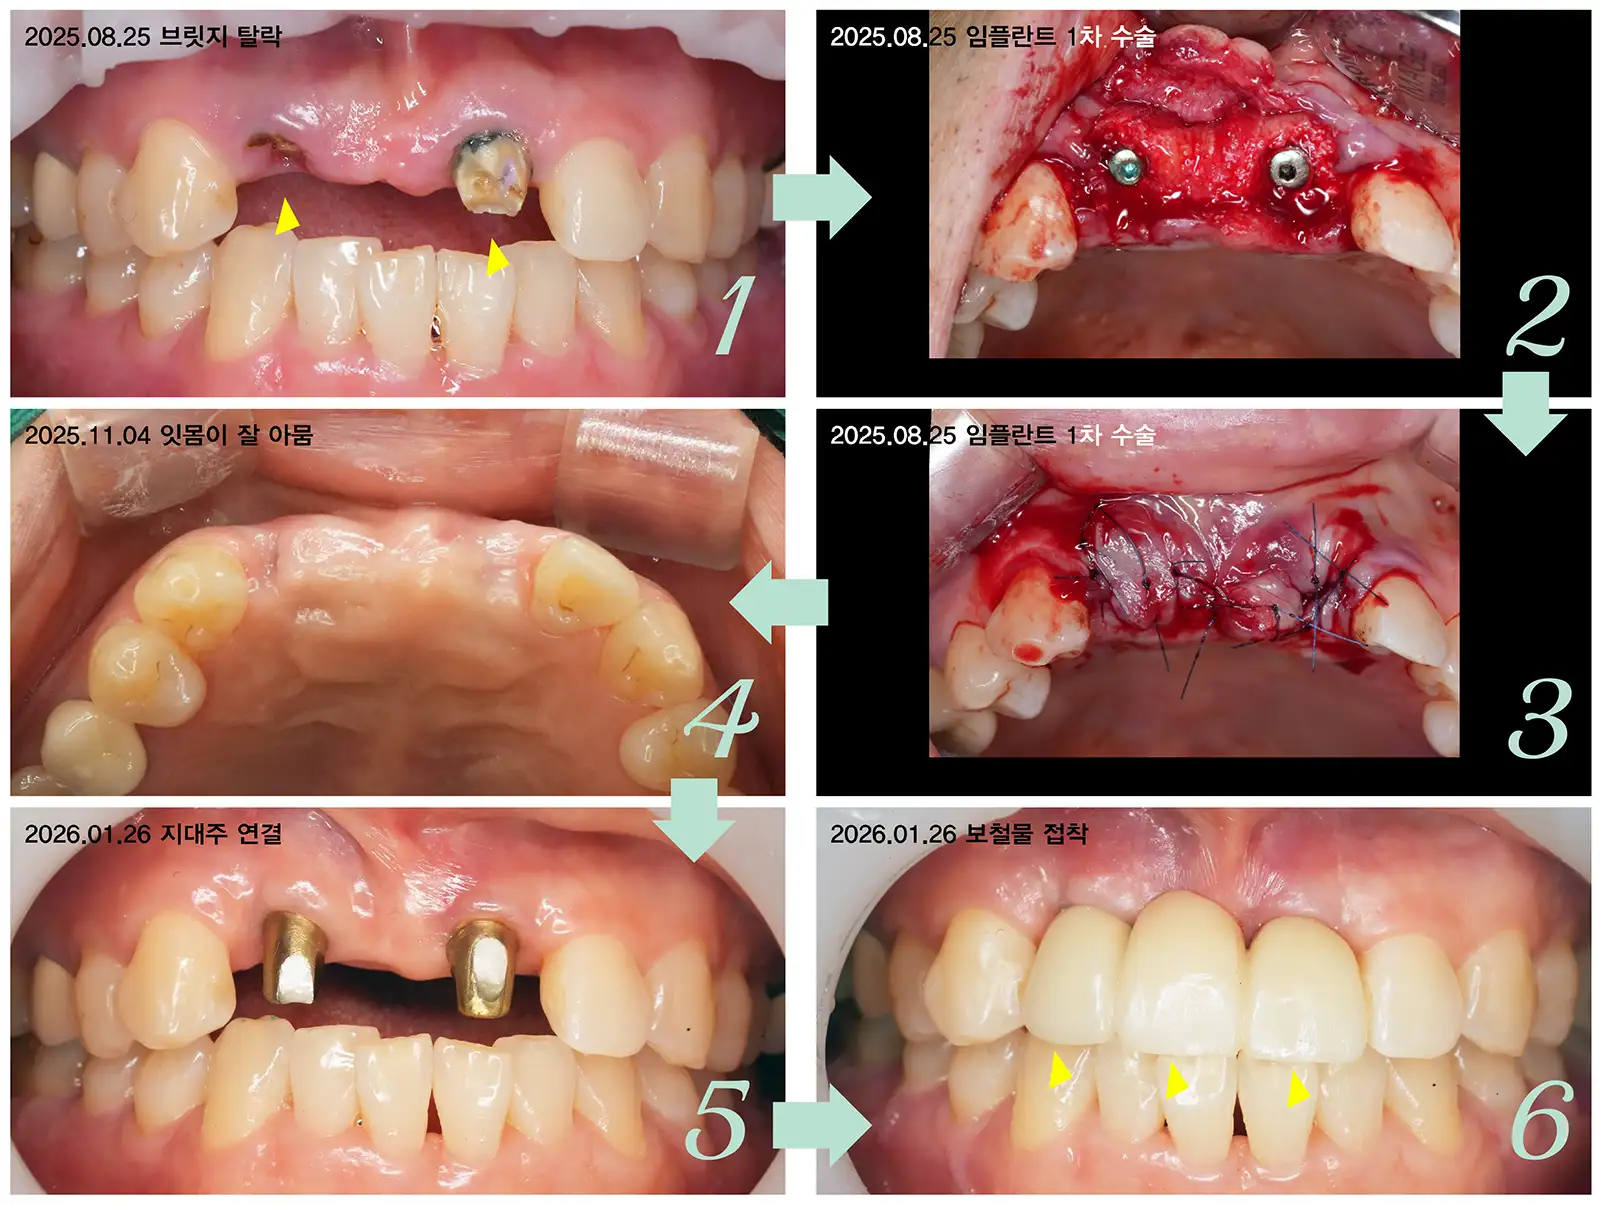

앞니 임플란트 브릿지 사례